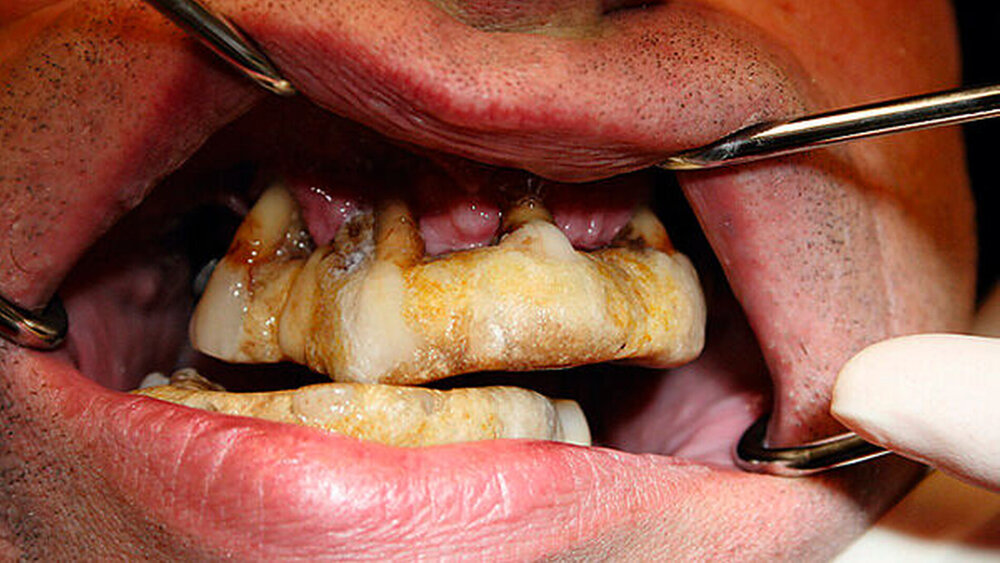

Mit auftretender Lockerung oder dem Herausbrechen einzelner Zähne klebte der Patient diese mit Sekundenkleber in einen über die Jahre entstehenden Komplex aus Sekundenkleber und Zahnstein wieder ein. Der Patient kaute demnach auf einer neu geschaffenen Okklusion und schuf sich ein künstlich neues Profil.